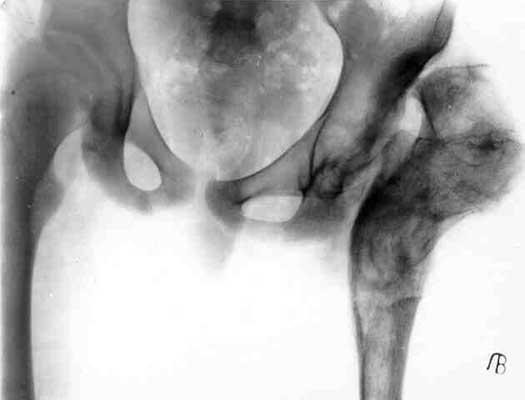

Pffd in children

Сhildren with PFFD